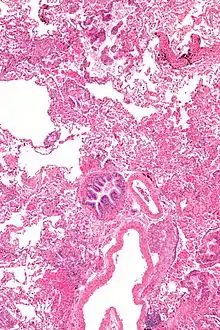

Grossly, LAM lungs are enlarged and diffusely cystic, with dilated air spaces as large as several centimeters in diameter.[105][106] Microscopic examination of the lung reveals foci of smooth muscle-like cell infiltration of the lung parenchyma, airways, lymphatics, and blood vessels associated with areas of thin-walled cystic change. LAM lesions often contain an abundance of lymphatic channels, forming an anastomosing meshwork of slit-like spaces lined by endothelial cells. LAM cells generally expand interstitial spaces without violating tissue planes but have been observed to invade the airways, the pulmonary artery, the diaphragm, aorta, and retroperitoneal fat, to destroy bronchial cartilage and arteriolar walls, and to occlude the lumen of pulmonary arterioles.[105]

There are two major cell morphologies in the LAM lesion: small spindle-shaped cells and cuboidal epithelioid cells.[107] LAM cells stain positively for smooth muscle actin, vimentin, desmin, and, often, estrogen and progesterone receptors. The cuboidal cells within LAM lesions also react with a monoclonal antibody called HMB-45, developed against the premelanosomal protein gp100, an enzyme in the melanogenesis pathway.[107] This immunohistochemical marker is very useful diagnostically, because other smooth muscle–predominant lesions in the lung do not react with the antibody.[108] The spindle-shaped cells of the LAM lesion are more frequently proliferating cell nuclear antigen positive than the cuboidal cells, consistent with a proliferative phenotype.[107] Compared with cigar-shaped normal smooth muscle cells, spindle-shaped LAM cells contain less abundant cytoplasm and are less eosinophilic. Estrogen and progesterone receptors are also present in LAM lesions,[109][110][111] but not in adjacent normal lung tissue.[112] LAM lesions express lymphatic markers LYVE-1, PROX1, podoplanin and VEGFR-3. The smooth muscle–like cells of AMLs are morphologically and immunohistochemically similar to LAM cells, including reactivity with antibodies directed against actin, desmin, vimentin, and HMB-45 as well as estrogen and progesterone receptors.[113][114] Unlike the dilated airspaces in emphysema, the cystic spaces found in LAM may be partially lined with hyperplastic type II cells.[115]